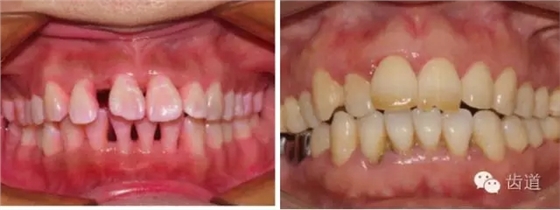

2、牙齦

(顏色、形狀、質地、退縮、BOP、PD、附著齦)